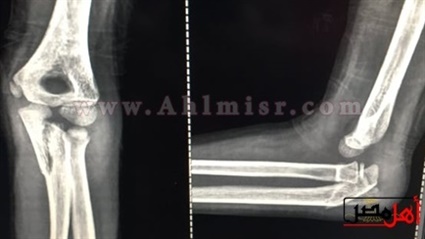

يقول أيسر فاروق والد الضحية، بدأت أزمة ابنتي حينما ورد إلى إتصال هاتفى من المدرسة الخاصة التى تدرس بها، ليخبروني بأنها سقطت فى المدرسة وأصيبت بكسر فى الذراع، ذهبت مسرعا إلى المدرسة وذهبت إلى خمس أطباء، واكتشفنا أن المفصل مخلوع والعظم مفتت ويحتاج إلى عملية كبيرة بسبب سقوط كبير تعرضت له ابنتي، لافتا إلى أن أحد الأطباء أخبرني أن السقوط الذى تعرضت له الطفلة سقوط كبير نظرا لأن وزن الطفلة لا يتناسب مع السقوط الذي تعرضت له لذا حدث تفتت بالعظام، مشيرا إلى أنه تم إجراء العملية الجراحية لابنتي واستخدم الأطباء الجبس والسلك نظرا لوجود تفتت بالعظام وهى ما يعد إحداث عاهة مستديمة.واستكمل، فقدت نجلتي النطق تماما لمدة 20 يوما وعلمنا من زملائها أن اثنين من زملائها بالمدرسة قاما بإسقاطها من الدور الثاني كانا هاذان الزميلان قاما بالتعدي بالضرب على ابنتي لعدة مرات فضلا عن سرقتهما لسندوتشات وعصائر ابنتي وقمت بالاستغاثة بالمدرسة.